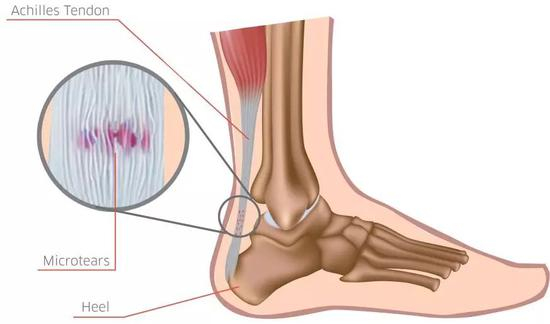

跟腱疼痛属于非常典型的过度使用损伤,在跑步过程中,跟腱要承受高达8-12倍体重作用;

也就是说跟腱受到了巨大力量的反复牵扯,导致轻微创伤反复发生,引发了跟腱力学衰竭,并随之发生结构改变,疼痛自然难以避免。

其实,跑友常常听说的“跟腱炎”这一术语并不准确,事实上跟腱局部并不存在炎症细胞,所以定义为“跟腱病”更为精准;

以下均采用更为科学的术语——跟腱病。

跟腱病频繁发生在两个位置:

(1)跟腱腱体上疼痛(距离跟腱止点近端2-6cm);(2)跟腱止点处疼痛。

其中,跟腱腱体的疼痛比较常见。